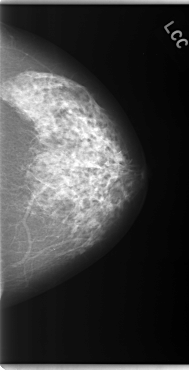

C_0085_1.LEFT_CC

LEFT_CC LINES 5912 PIXELS_PER_LINE 3024 BITS_PER_PIXEL 12 RESOLUTION 50 NON_OVERLAY